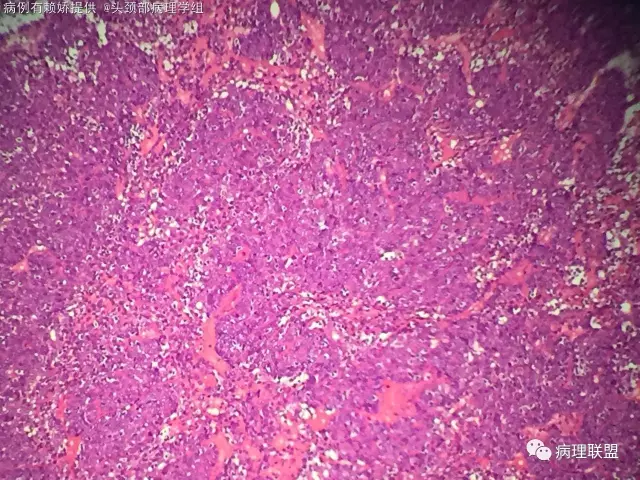

男,54岁,后颈部肿块10年(病例由赖娇 提供,致谢!)

小汗腺螺旋腺瘤

@梅宜兼 本例明显呈上皮巢排列,肿瘤由两种细胞构成外层呈栅栏状排列细胞小核染色深,另一种为咯略大淡染隐约可见小核仁的腺上皮细胞!间质可富裕血管,水肿及少量基底膜样物质!另外还有个特点散在淋巴细胞!该肿瘤肉眼看切片给人第一印象像个淋巴结!